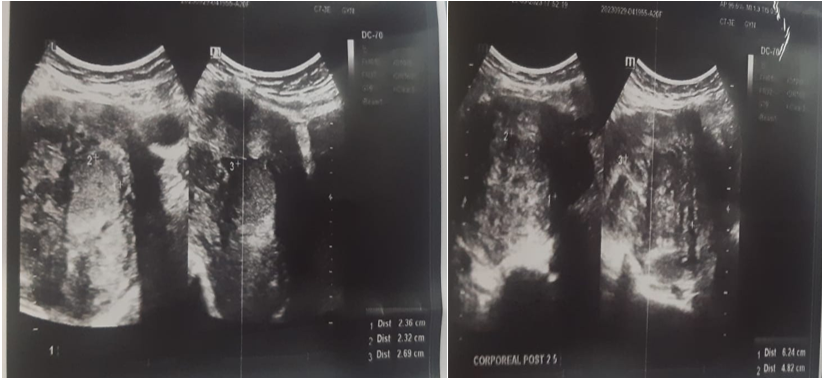

Pelvic ultrasound revealed an enlarged uterus measuring 145x84x80mm with bumpy contours and heterogeneous echostructure with the presence of multiple heterogeneous hypoechoic myomas of variable size, the largest of which was corporal-fundial measuring 62x59x48mm classified FIGO 2-5 and a submucosal myoma measuring 27x23x23m classified FIGO 1.

Fig 5: Pelvic ultrasound revealed multiple heterogeneous hypoechoic myomas.

Pelvic MRI revealed a polymyomatous uterus, with a FIGO 2-5 resorbed fibroid occupying almost the entire uterine cavity, and a small FIGO 6 subserous myoma measuring 28x21 mm.

Fig 6: MRI suggestive of polymyomatous uterus